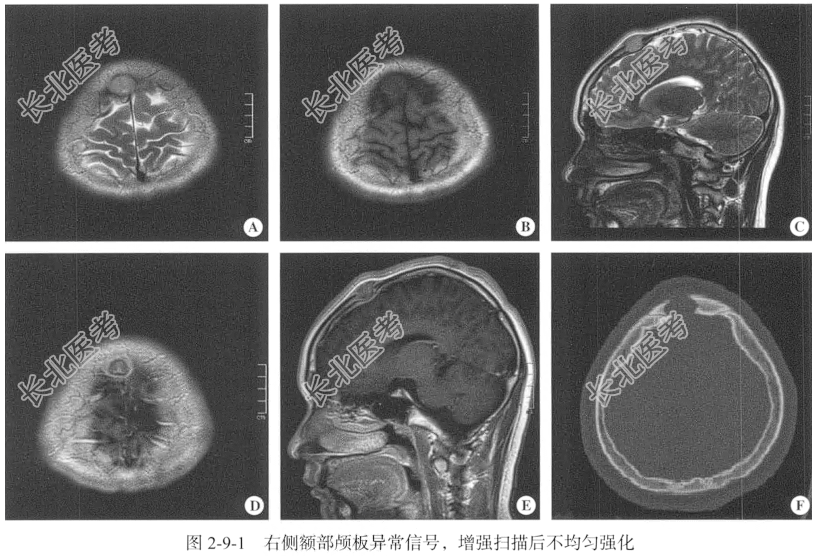

【专科查体】头颅大小正常,额部可见一大小约5cm×5cm的皮下结节,质地韧,边界清,活动度不良,有触痛,无波动感,表面无破溃。

【头颅MRI检查】仰卧位,横断位扫描,包括T₁WI、T₂WI及T₂WI FLAIR序列,扫描范围自小脑半球至颅顶以下,扫描层厚为6mm,层间隔0.5mm,矩阵256×512;辅以矢状位T₂WI序列,平扫后行横断位、冠状位及矢状位的增强扫描。

【影像图片】见图2-9-1。

【手术所见】剥离骨膜后见皮下有肿瘤组织,肿瘤大小约为3cm×2cm×3cm,呈黄白色,质硬,血供不丰富,肿瘤与周围组织界线清,粘连紧密,将肿瘤组织与骨瓣一起取下,剔除残余肿瘤组织,将肿瘤组织送检。

【病理所见】肉眼所见:右额顶骨肿瘤,不规则组织一块,大小约为5cm×4cm×1cm,表面灰白色,切面中央见一肿物,大小约为2cm×1cm×0.8cm,灰红色。镜下可见朗格汉斯细胞呈卵圆形,核不规则、有核沟和核折叠,核仁不明显,核膜薄,细胞质中等量,略呈嗜酸性,伴程度不等的嗜酸性粒细胞浸润(图2-9-2)。免疫组化结果:Ki-67(3%~5%+),Langerin(+),S-100(+)、CD1a(+),CD163(散+),CD68(+)。

【病理诊断】嗜酸性肉芽肿。